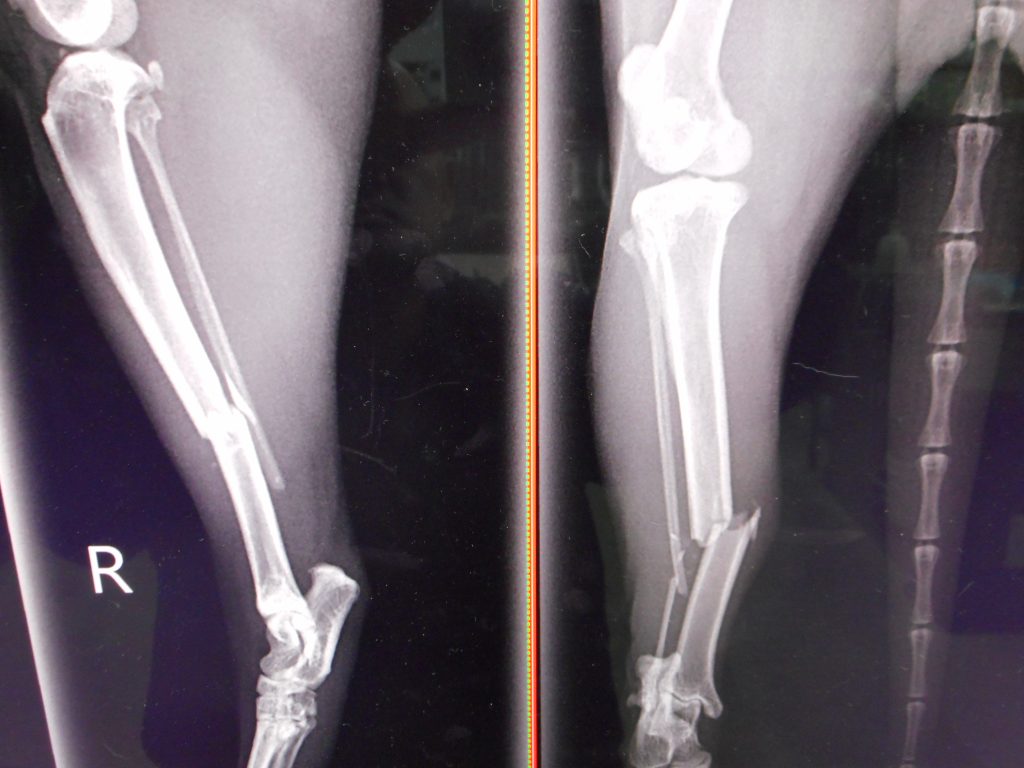

キャットタワーから落下事故です

ケージに後肢がはさまったんでしょうね

約10歳の猫